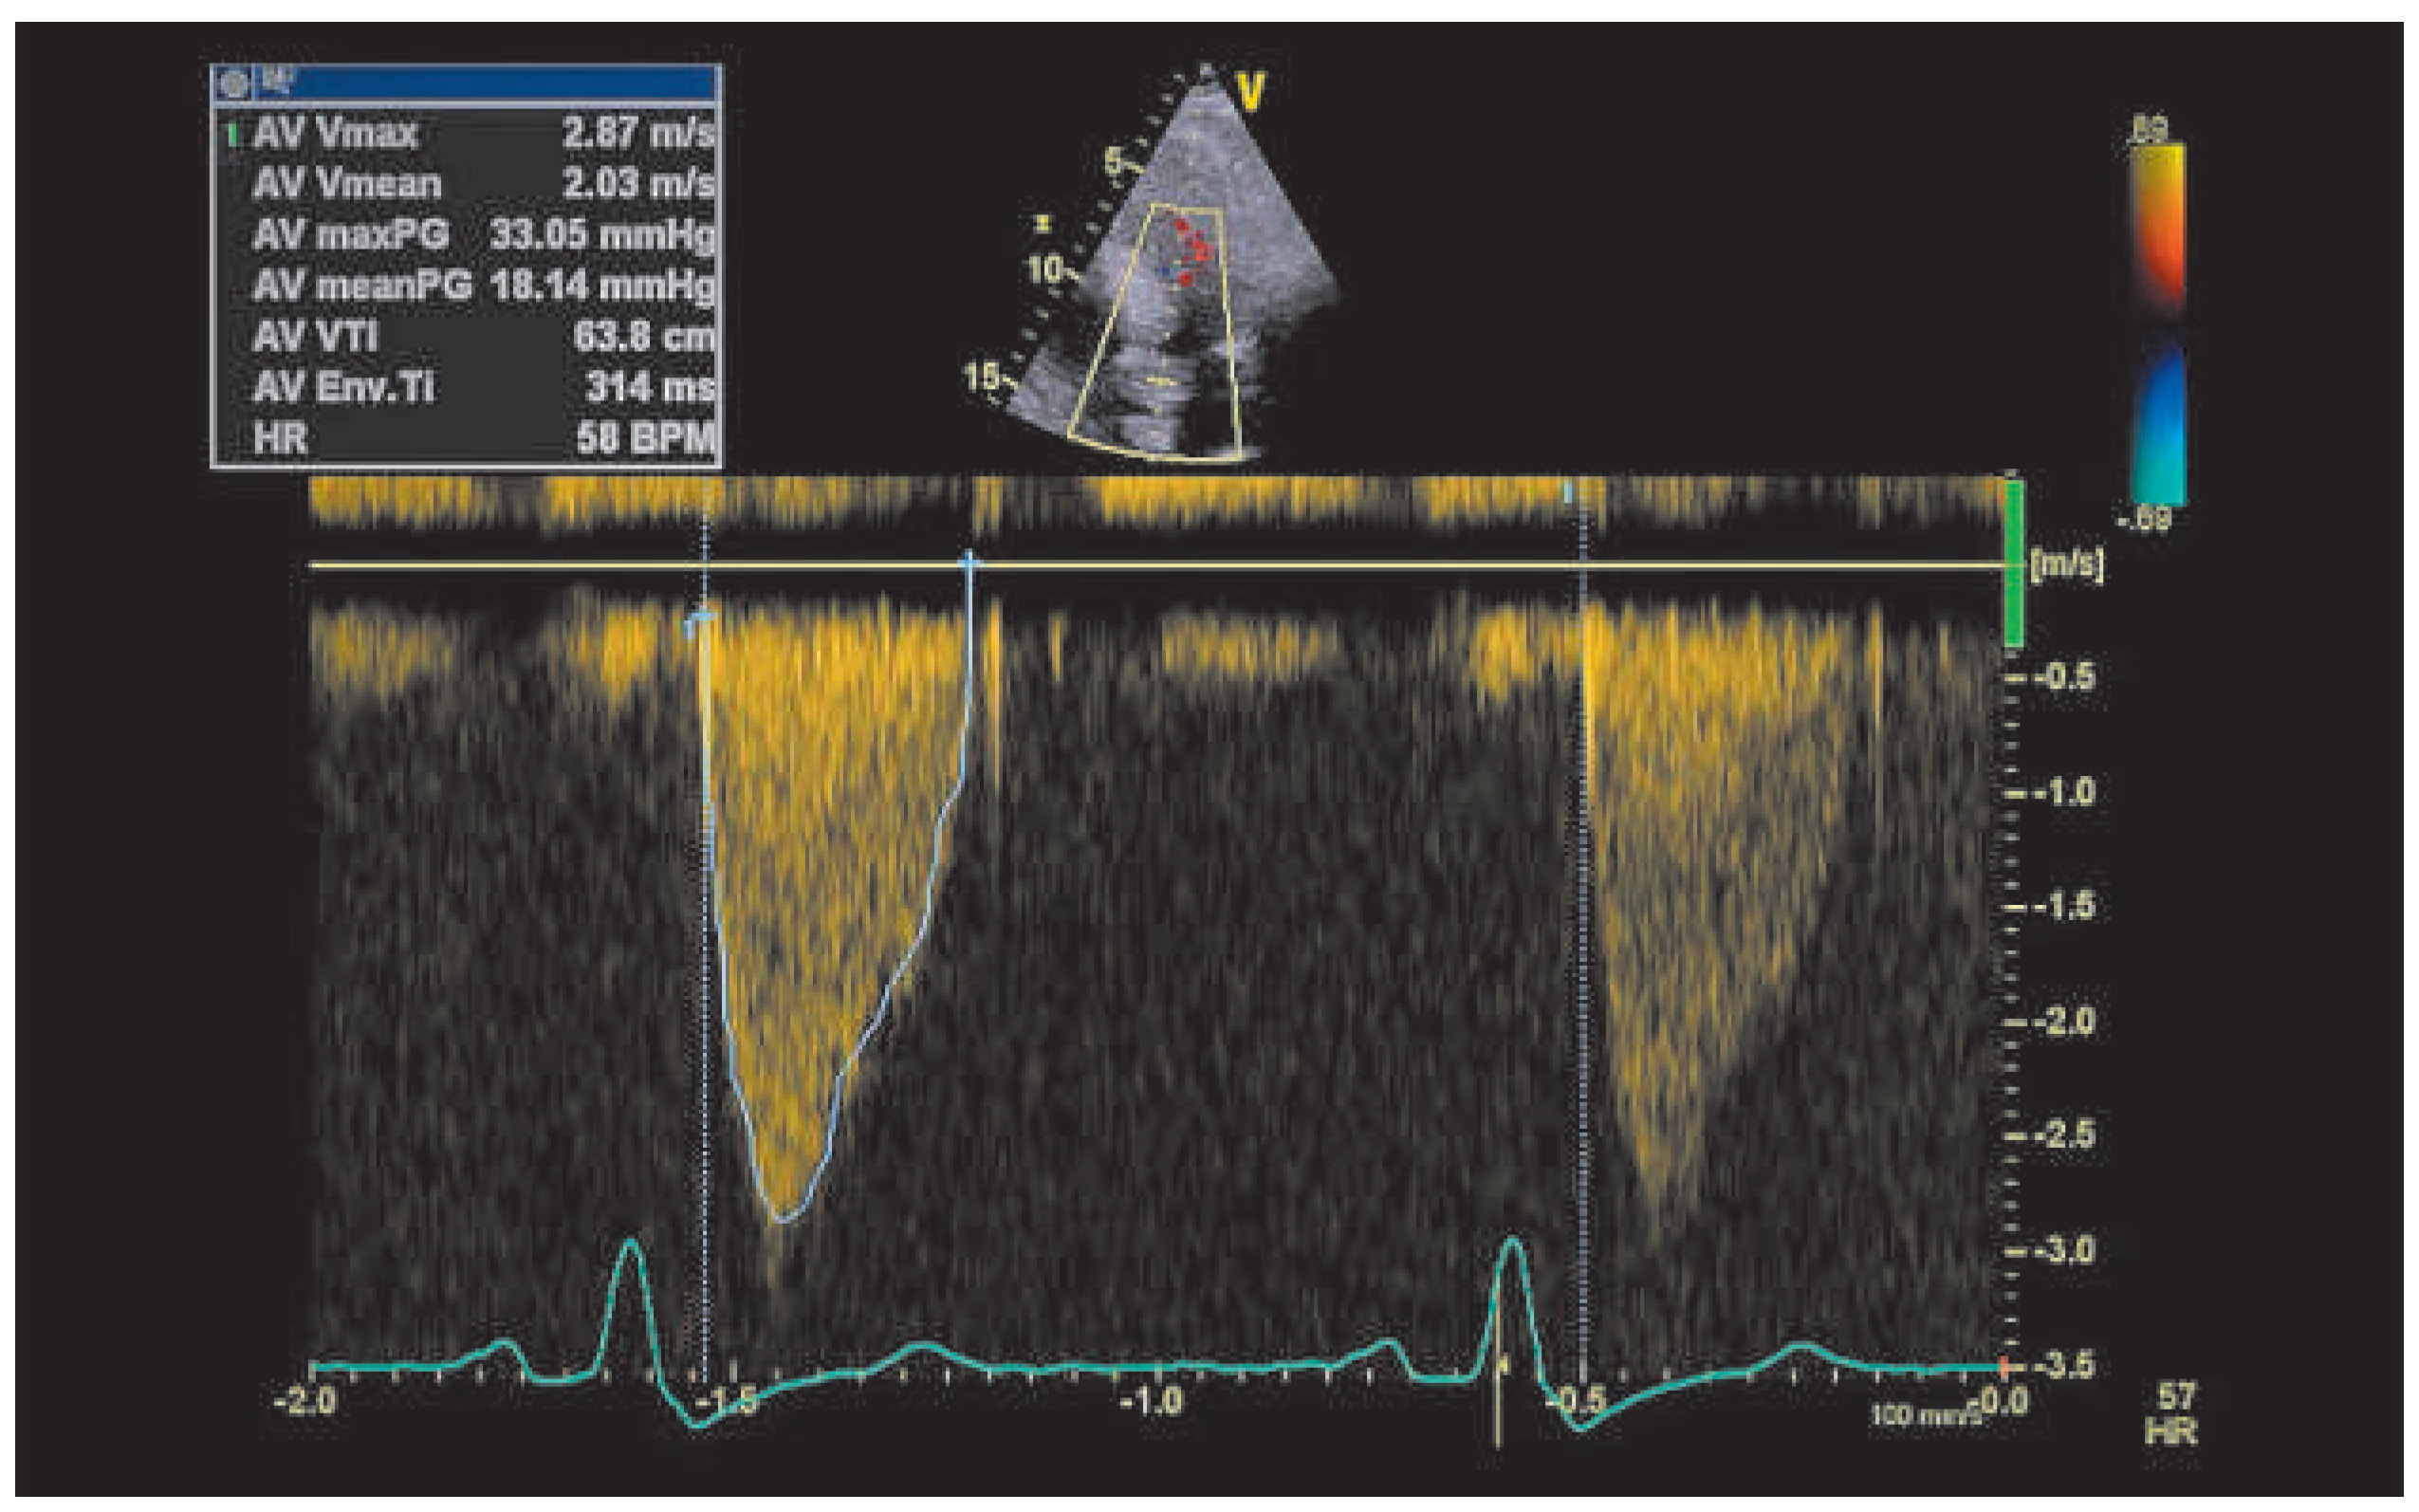

Case report